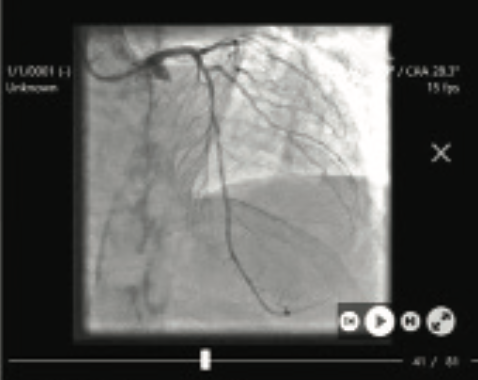

Virtual FFR: A Simple, Reliable, Angiography-Based Method to Assess Physiological Lesion Severity in the Cath Lab

Percutaneous coronary intervention (PCI) in stable coronary disease can improve quality of life and may reduce type 1 MI.1 Identifying significant coronary lesions that will benefit from PCI can sometimes be challenging. FFR is the gold standard for evaluating the functional significance of a coronary lesion.2 Fractional flow reserve (FFR)-guided PCI has been shown in multiple studies to improve clinical outcomes and coronary physiology can lead to reclassification of treatment strategy in up to 40% of cases.3,4 Despite the undeniable utility of an FFR-guided treatment strategy it remains underutilized in clinical practice due to several disadvantages. FFR requires extra equipment, time, and medication administration, making its use cumbersome in a busy clinical practice.